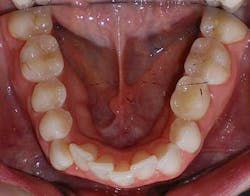

A 27-year-old female presented with a chief complaint of crowding on the upper and lower arches. Upon evaluation, it was noted that the patient had 2 mm and 4.5 mm of maxillary and mandibular arch length deficiency respectively, a missing lower left second bicuspid with primary tooth still present, small upper lateral incisors, cross-bite of the lower right canine, and lower midline shift to the right of 2 mm. (Figs. 1-8)

Figs. 1-8